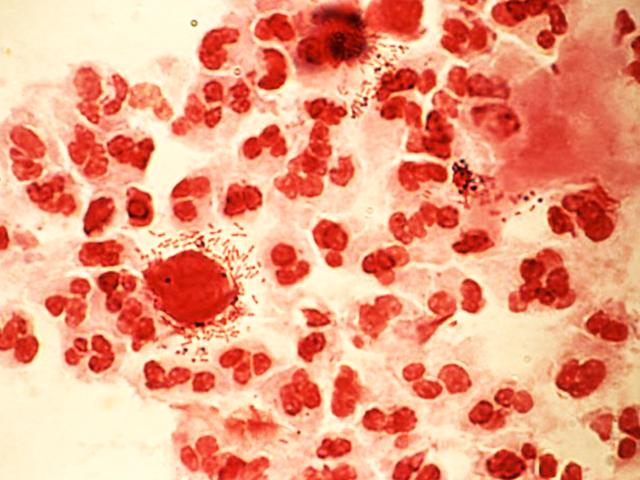

Хотя болезнь имеет «говорящие» признаки, перед тем как лечить трихомониаз у женщин, следует провести лабораторные анализы. Диагностика проводится одновременно несколькими способами, что повышает шансы на обнаружение всех видов патогенной микрофлоры. К обязательным исследованиям относят мазок на флору из влагалища, бактериальный посев мочи, анализ венозной крови методами ПЦР или ИФА. Если обследование выявит несколько возбудителей, потребуется комплексный подход к лечению, то есть принимать лекарства придется по определенной схеме.